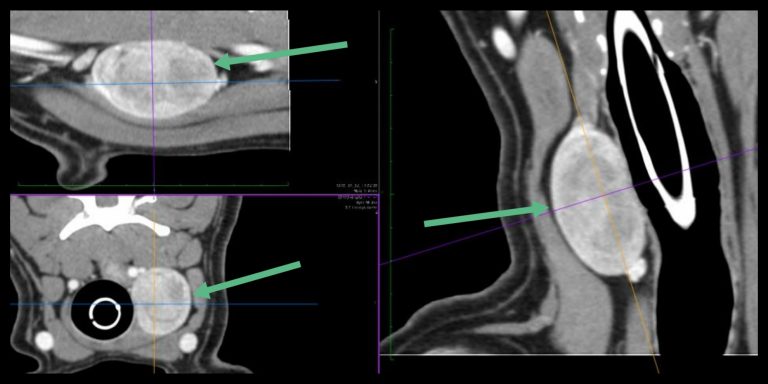

Kutyákban az elváltozás pontos eredetének, méretének, valamint a környező szövetekkel való összefüggésének megítélésére CT vagy MRI vizsgálat szükséges, mert ezeket pusztán tapintásos vizsgálattal nem lehet biztosan megítélni! A mellkas CT vizsgálatának kiemelt jelentősége van az áttétkeresésben is.

Kutya daganatos pajzsmirigyének CT felvétele, a Fuziovet Állatkórház jóvoltából